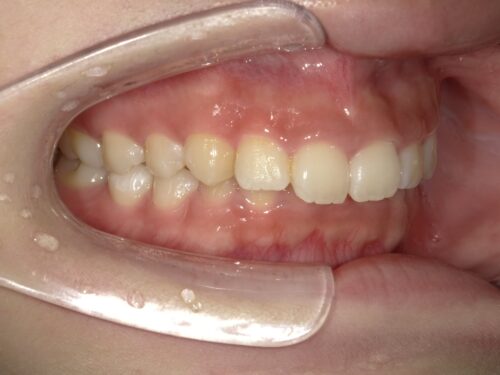

治療前・左側の写真

治療前・右側の写真

横から見ると、上下の前歯の位置関係がよりはっきりと分かります。上の前歯がかなり前方に出ていますね。